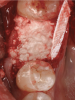

The patient shown in Figure 1 had presented after significant endodontic-related abscesses reduced the height of both buccal and lingual plates of bone. Covering the biphasic calcium sulfate (BPCS) graft with a dense polytetraflouroethylene (PTFE) barrier for 3 weeks enhanced healing in the site. Clinically, it is apparent that the ridge volume was maintained over 5 years and supported keratinized tissue (Figure 2). Most importantly, there was, on histologic evaluation, 58% vital bone, with no remnants of the bone replacement graft material (Figure 3).

Fig 1. A significant loss of bone necessitated covering the BPCS with a dense PTFE barrier.

Figure 1